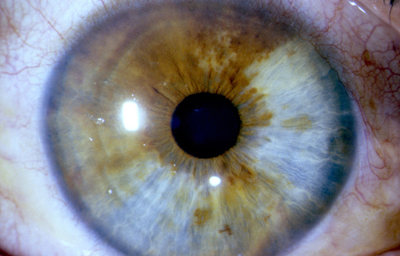

Anomalias del Estroma: Hiperplasia, Hipoplasia

Hiperplasia

Archivo fotográfico Dr. Francisco Barraquer.

Hipoplasia

Archivo fotográfico Dr. Francisco Barraquer.